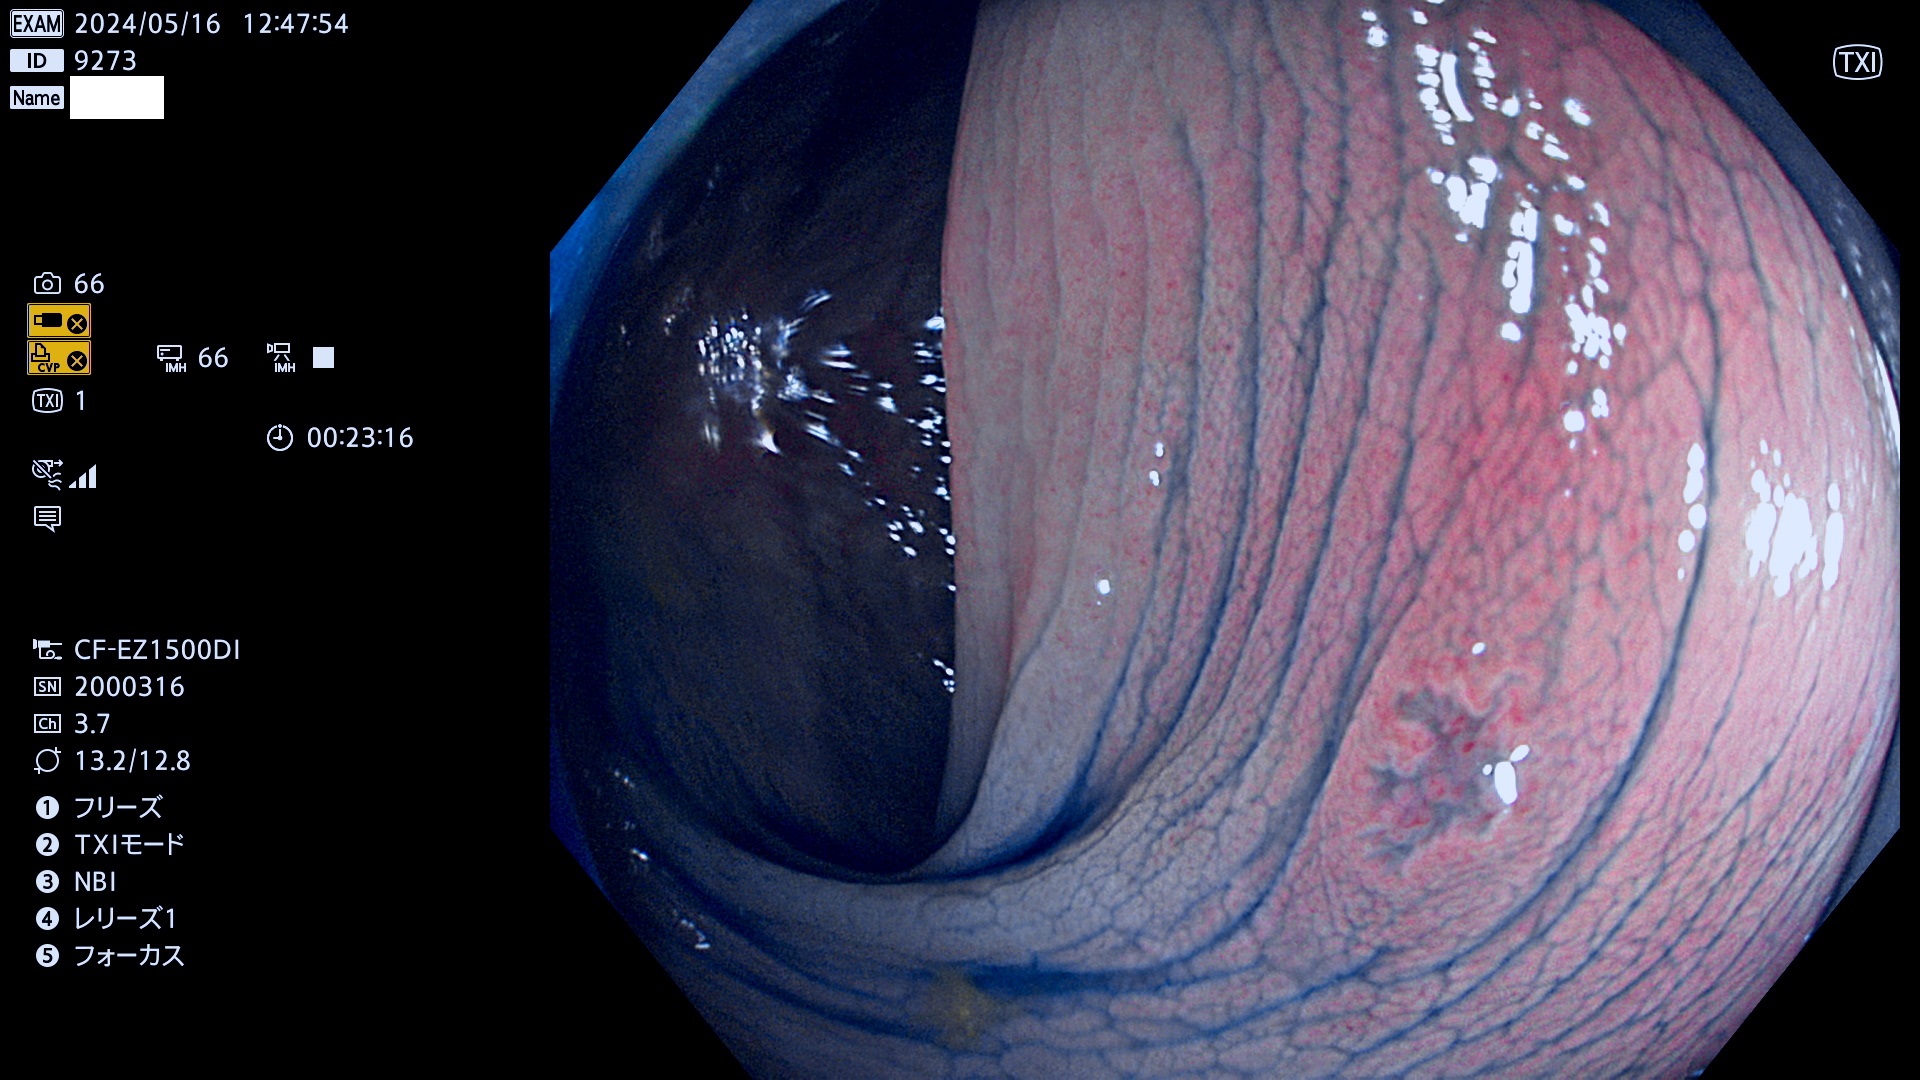

表面型腺腫(Flat Adenoma)の中で、完全に平坦な物をUb、陥凹している物をUcと呼びます。平坦隆起型(Ua)よりも、発見が難しく危険な病変です。

毎週の検査(木・金・土・日)に発見されたUb、Uc型・腺腫を、その週の日曜の夜にUPし1週間、提示します。

抽出の対象期間 2024年5月16日〜5月19の4日間(40件の検査)10件 (10/40=25%)